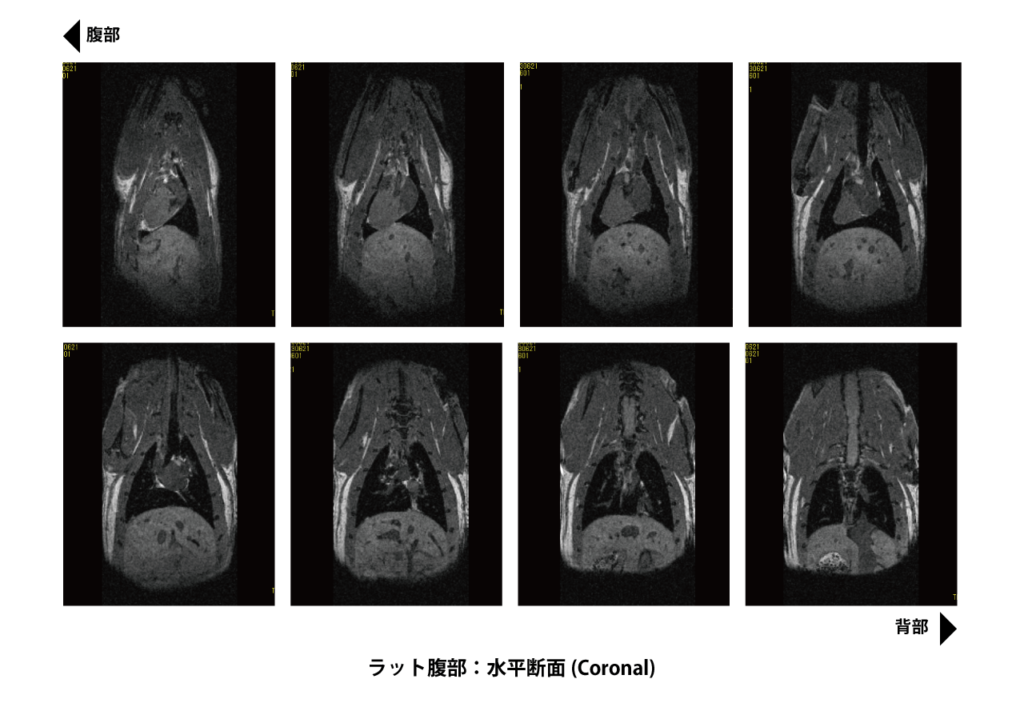

MRI検査 | きたがわ脳神経外科 | 北九州市八幡西区本城学研台の。APERTO Inspireと“癒し”を与える独自のシステムで快適なMRI検査。検査機材について|動物検診センター キャミック | 動物検診。検査機材について|動物検診センター キャミック | 動物検診。緑と黒のドレスを着た女性のポートレート